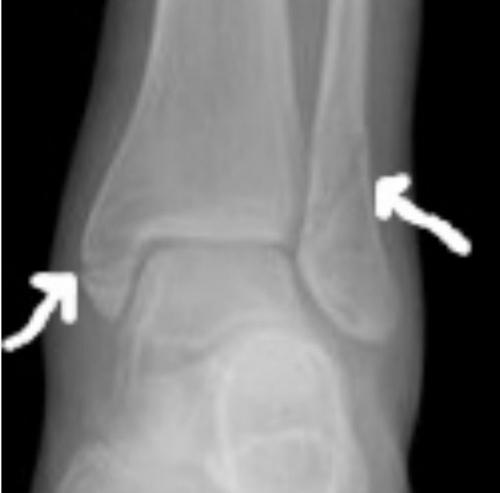

Переломы хорошо видны на рентгенограммах.

Двойная проблема

Косвенные признаки повреждения мягких тканей:

- суставная щель асимметрична;

- межберцовое расстояние увеличено;

- таранная кость смещена.

Для уточнения диагноза проводится рентгенологическое исследование в трех проекциях.